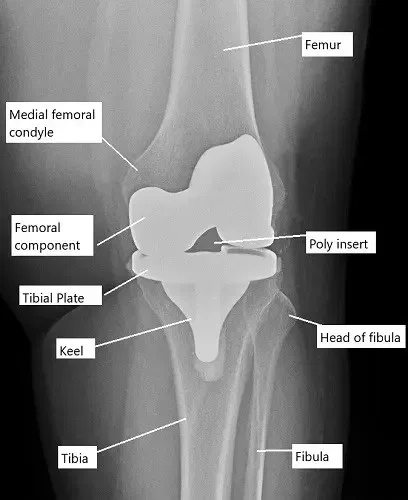

The knee joint is a hinge joint formed by the femur (thigh bone), tibia (shin bone), and patella (kneecap). The femur and tibia are covered with articular cartilage to allow smooth movement, and the patella glides over the femoral surface. Knee replacement surgery involves removing the damaged portions of these bones and replacing them with prosthetic components. These prosthetic components are either fixed with bone cement (cemented) or press-fitted into the bone (cementless), and they restore the function and mobility of the knee joint.

X-ray showing total knee replacement.